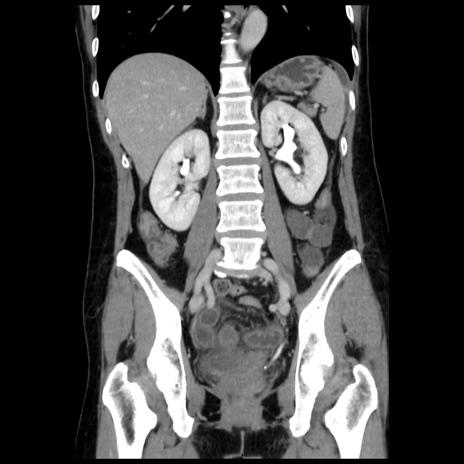

症例10(冠状断像)

【症例】 50歳代女性

【主訴】 腹痛

【現病歴】前日生レバーを食べた。今朝に排便あり。 昼前に突然発症の腹痛を生じ、当院救急外来を受診した。

【既往歴】 子宮筋腫にてで子宮全摘後

【身体所見】 意識清明、腹部:平坦、軟、下腹部やや左を中心に圧痛・反跳痛あり、筋性防御あり

【データ】WBC 7800、CRP 0.07